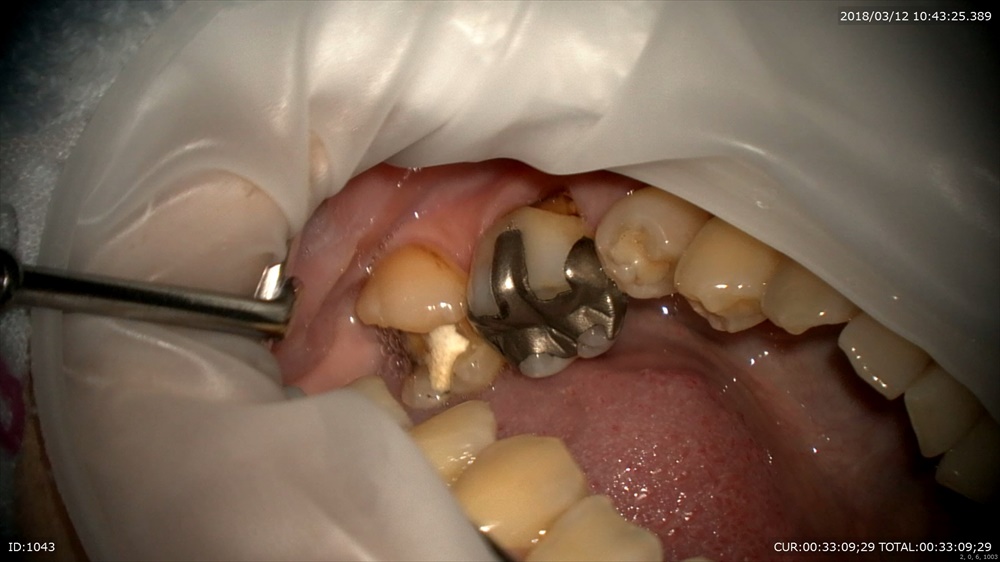

最後は銀場虫歯の方

重症と診断した時点でラバーダム。無菌的治療は必須!

感染をとり

MTA

これで痛みが出なければ大丈夫!!